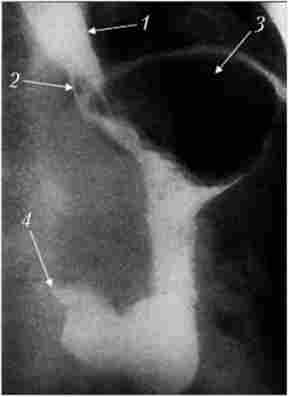

Хірургічне лікування. При кардіоспазме найбільш поширені езофагокардіоміо- Вакуя (операція Геллера) і її численні модифікації. Розсічення м'язової оболонки дистального відрізка стравоходу усуває нерасслабленіе НПС при ковтанні. Сучасний варіант операції Геллера передбачає розсічення м'язової оболонки вертикальним розрізом на передній стінці стравоходу з невеликим (1-2 см) заходом на кардіо (рис. 9.5).

Езофагокардіоміотомії по Геллеру. Етап відділення слизової оболонки від м'язового шару стравоходу і кардії

Мал. 9.5. Езофагокардіоміотомії по Геллеру. Етап відділення слизової оболонки від м'язового шару стравоходу і кардії:

1 - стравохідний отвір діафрагми; 2 - стравохід; 3 - нерозкриті слизова оболонка стравохідно-шлункового переходу; 4 - шлунок